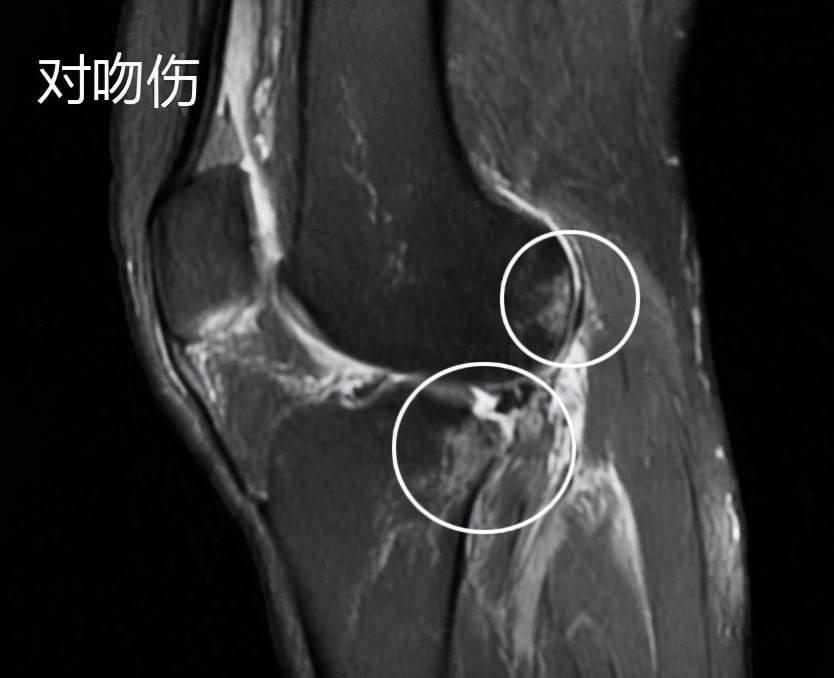

另外老人的前交叉韧带真的像预估的一样,发生了明显的撕裂,我们可以看到在核磁影像上有经典的对吻伤,也就是说韧带撕裂的时候,股骨远端与胫骨平台发生了撞击,造成了骨头的挫伤,在骨头内可以看到明显的水肿信号。

而且,前交叉韧带也撕裂了,半月板在核磁影像上看起来还是比较不错的。